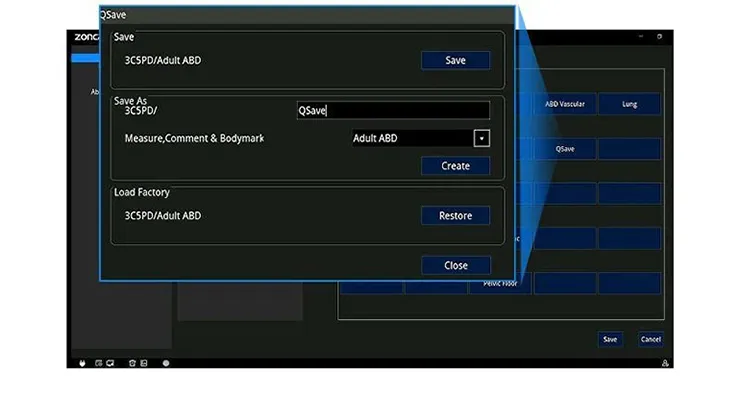

Эффективный и быстрый рабочий процесс

- предварительные настройки для различных исследований разных видов животных на всех датчиках

- программируемые настройки с возможностью сохранения в библиотеке

- ведение базы данных исследований животных

- автоматическое формирование отчета по проведенным исследованиям

- печать отчета, экспорт отчета на USB, DICOM-сервер